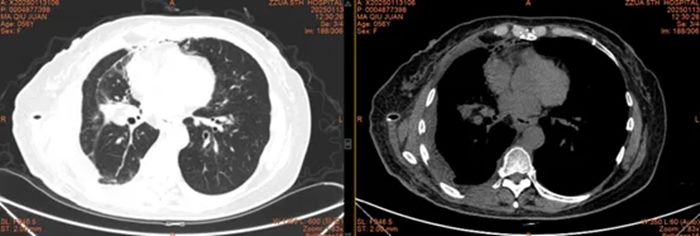

术后CT

患者术后恢复良好,马女士及其家人激动地向高主任表达了深深的谢意。如今,患者现已顺利康复出院,回归正常的生活。